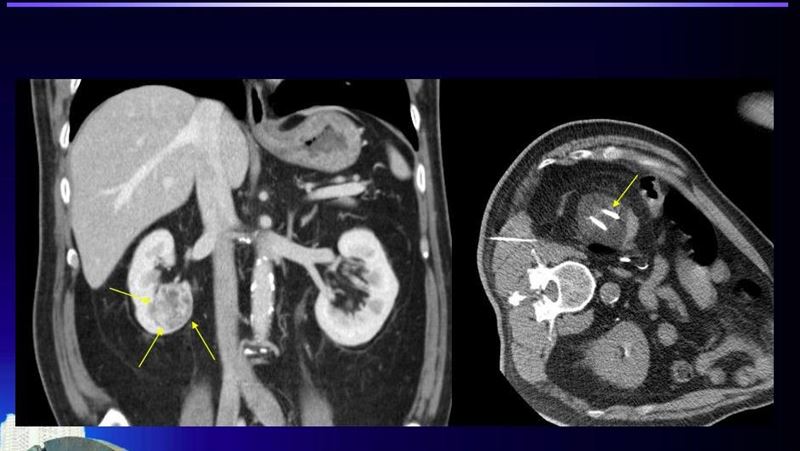

▲北榮團隊冷凍消融治療過程。(圖/記者簡浩正攝影)

她說,以「氬氦刀冷凍消融術(簡稱冷凍消融術)」為例,是在電腦斷層導引下,將冷凍探針經過皮膚插到腫瘤組織中,冷凍探針在針尖可形成一圓型的超低溫範圍,當溫度低於-20℃即可造成細胞壞死,達到治療目的。透過氬氣在針體內腔急速壓縮,瞬間使局部溫度降低到零下160℃。腫瘤組織降溫後,細胞內和細胞外迅速形成冰晶,導致腫瘤細胞破裂。整個過程皆在影像監控中,確保腫瘤完整被冰球包覆,不損傷正常組織。治療後恢復時間快、副作用小,並具有潛在可以刺激抗體生成的效果。

沈書慧強調,冷凍消融術一般來說對於4公分以下的小型腫瘤,可達到跟手術相當的療效。與傳統手術比較,侵入性較小,沒有傳統的開刀傷口,身上只會幾個針孔;恢復時間很短,疼痛也較輕微,通常在治療過後即可正常活動,隔天就能出院。不過她也提醒,有嚴重的凝血功能障礙、已經侵犯至腸道的腫瘤、已經侵犯至血管腔內等患者,因恐致腸道破裂與術後效果不佳,不適合接受冷凍消融術。